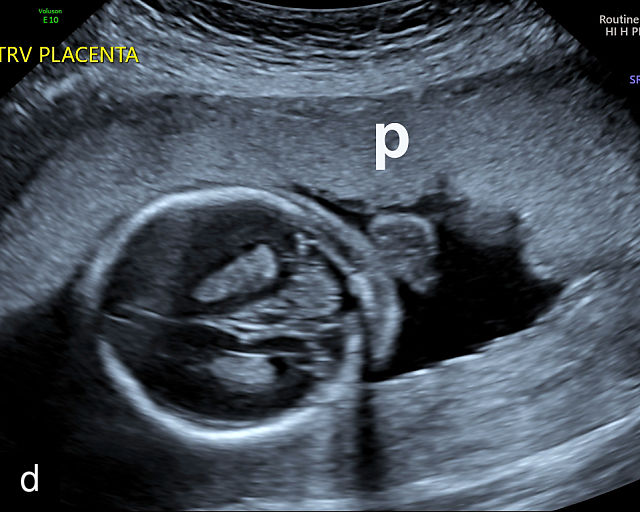

In the early first trimester, trophoblastic tissue appears as an echogenic ring encircling the gestational sac (Figure 1a). By the late first trimester, the placenta becomes recognizable as a distinct structure on ultrasound (Figure 1b). Initially, it presents as a homogeneous echogenic mass (Figure 1b–d) but undergoes progressive differentiation, becoming more heterogeneous as pregnancy advances from the second to third trimester (Figure 1e–g). By the third trimester, cotyledons become discernible, and in the late third trimester, calcifications frequently appear basally and around the cotyledons (Figure 1g).

1

Ultrasound images of development of the placenta (P/p). (a) Trophoblastic tissue appearing as an echogenic ring surrounding the gestational sac at 6 weeks' gestation. (b) Placenta at 12 weeks has become a discrete, uniformly echogenic mass. (c) Placenta at 17 weeks. (d) Placenta at 20 weeks. (e) Placenta at 27 weeks. (f) Placenta at 33 weeks. Increasingly, differentiation and heterogeneous appearance is seen, with demarcation of the cotyledons. Basal calcifications are beginning to appear. (g) Placenta at 40 weeks, showing a distinctly heterogeneous appearance, with clear demarcation of the cotyledons and presence of calcifications.